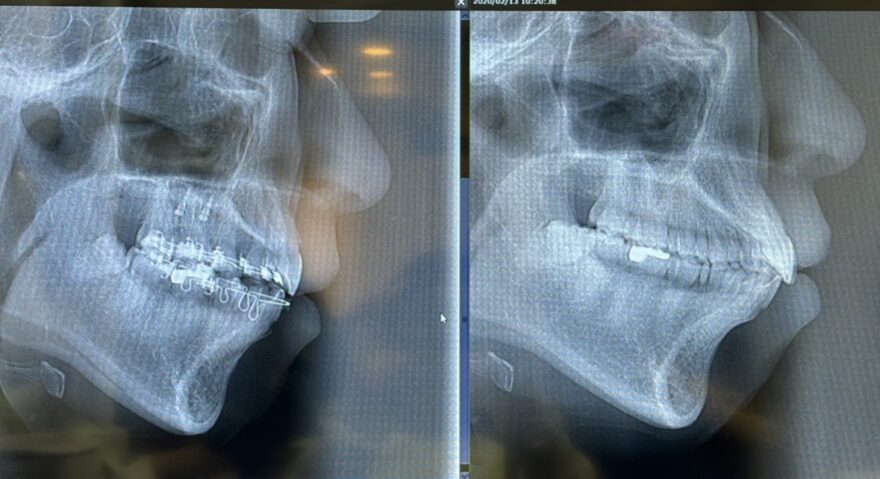

◎スタッフの矯正治療中のレントゲン。上顎の前突が治り、全体的に後方に下がっています。顔の輪郭も印象も変わりますよ!